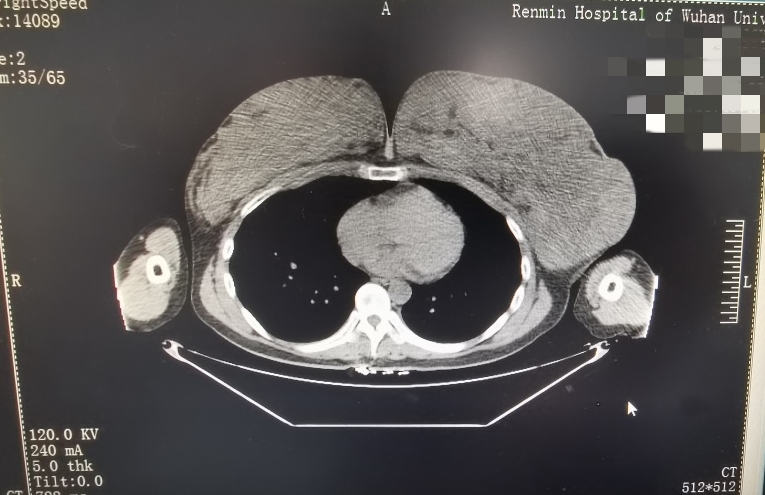

针对杨女士的病情,该院乳腺甲状腺中心联合整形美容外科进行了多次讨论,经过彩超、CT等系列诊查,初步诊断杨女士为左乳结节,乳房肥大症(巨乳症),乳房体积明显增大,乳腺腺体结构紊乱伴增生。